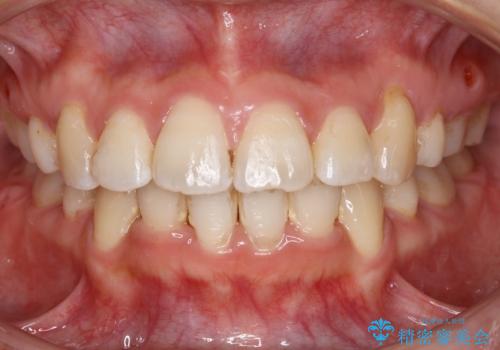

[ セラミック治療 ] 前歯の見た目を改善したい

担当医 大元洋佑